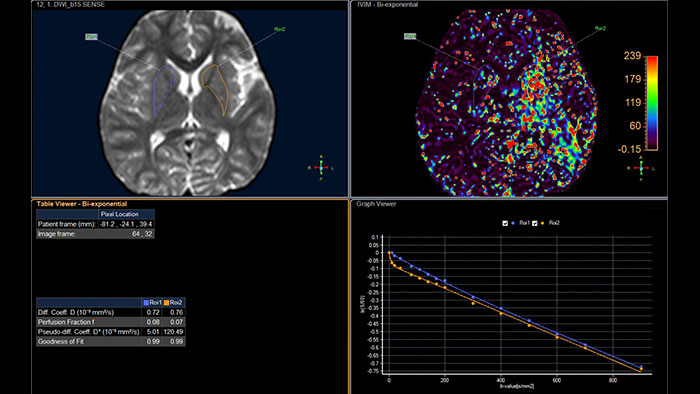

Computed diffusion weighted images at a b-value of choice

The application is intended to view, process and analyze MRI Diffusion Weighted Images. It calculates and displays cDWI at a

b-value of choice (from 0 to 5,000 s/mm2) and provides advanced supportive analysis and visualization tools of diffusion MRI images and parametric maps.